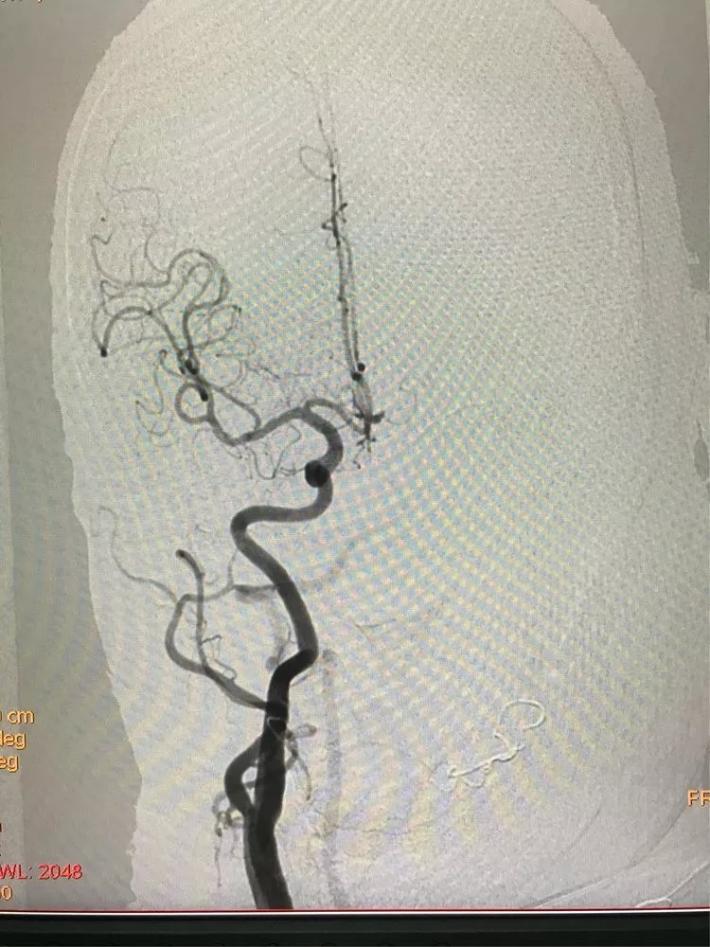

MRA检查显示:基底动脉闭塞。

桥接动脉取栓,造影显示:基底动脉闭塞。

微导管进入基底动脉尖部,显示进入真腔。

置入支架,见基底动脉有血流。

取出支架,血管闭塞。

第二次上微导管进入真腔。

置入支架,基底动脉有血流。

取出支架,血管未开通。

第三次上微导管。

支架打开取栓。

见基底动脉血流恢复,左侧大脑后动脉血流欠佳。